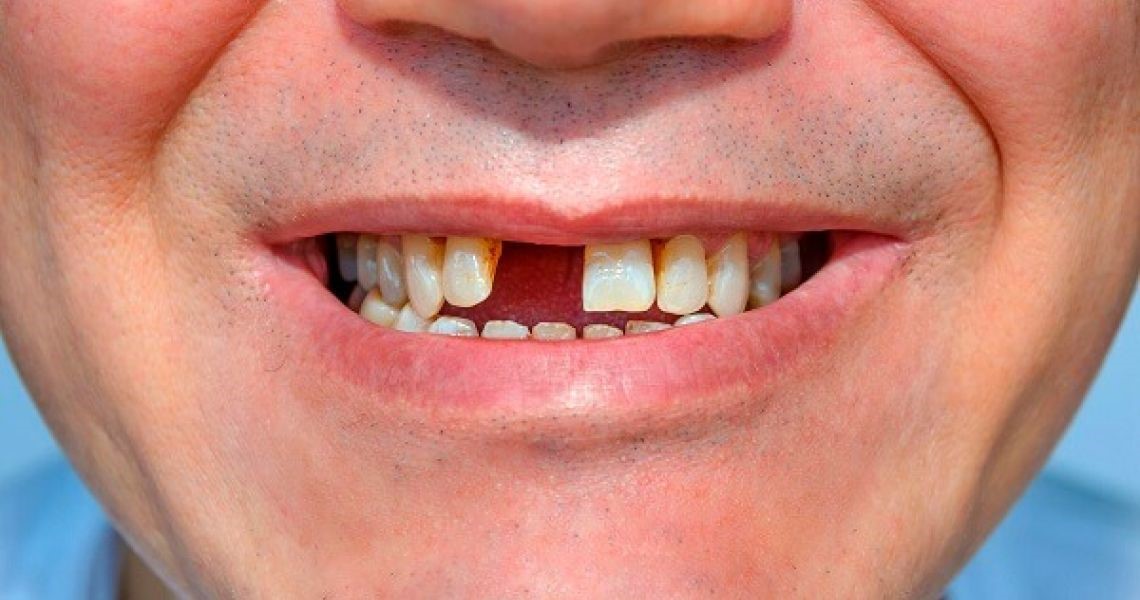

Trong nha khoa hiện đại, độ chính xác là chìa khóa quyết định thành công của một ca cấy ghép Implant. Và tại Nha khoa Như Ngọc, chúng tôi ứng dụng những công nghệ tiên tiến nhất để đảm bảo...